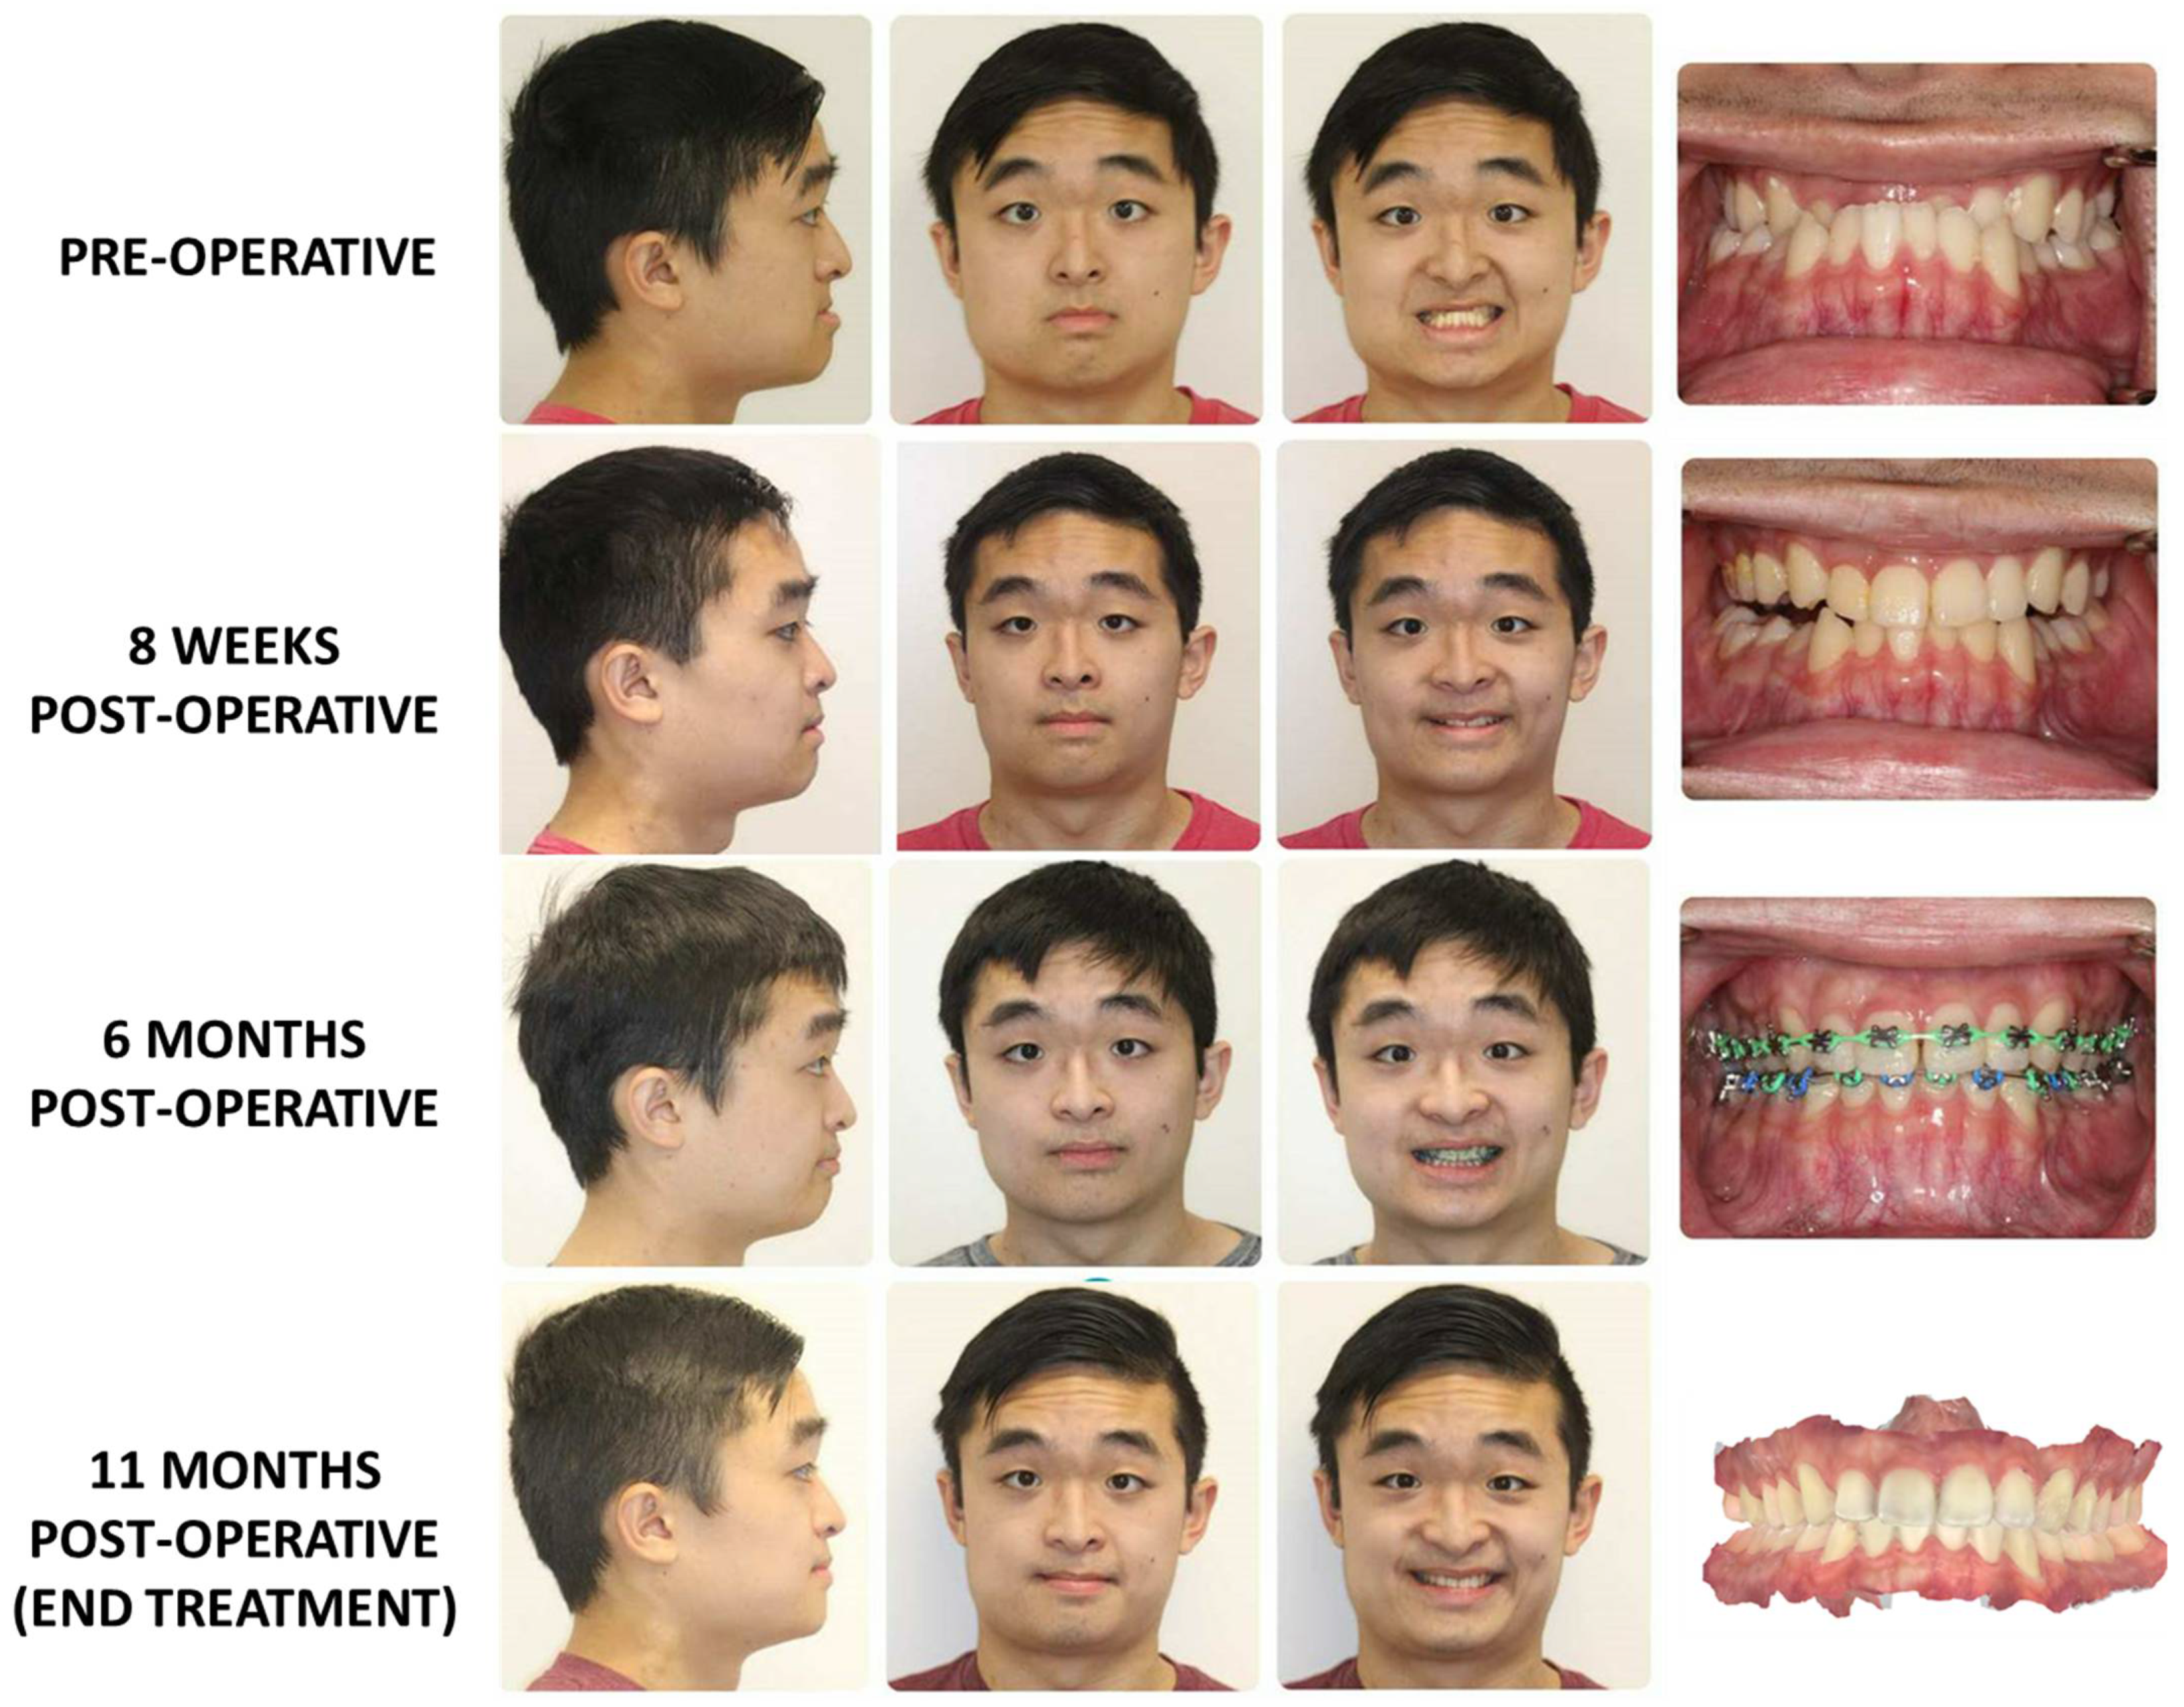

3.2. Surgery First Protocol (Figure 5)

3.3. Surgery-Only Protocol (Figure 6)

3.4. Clear Aligner Therapy (Figure 7)